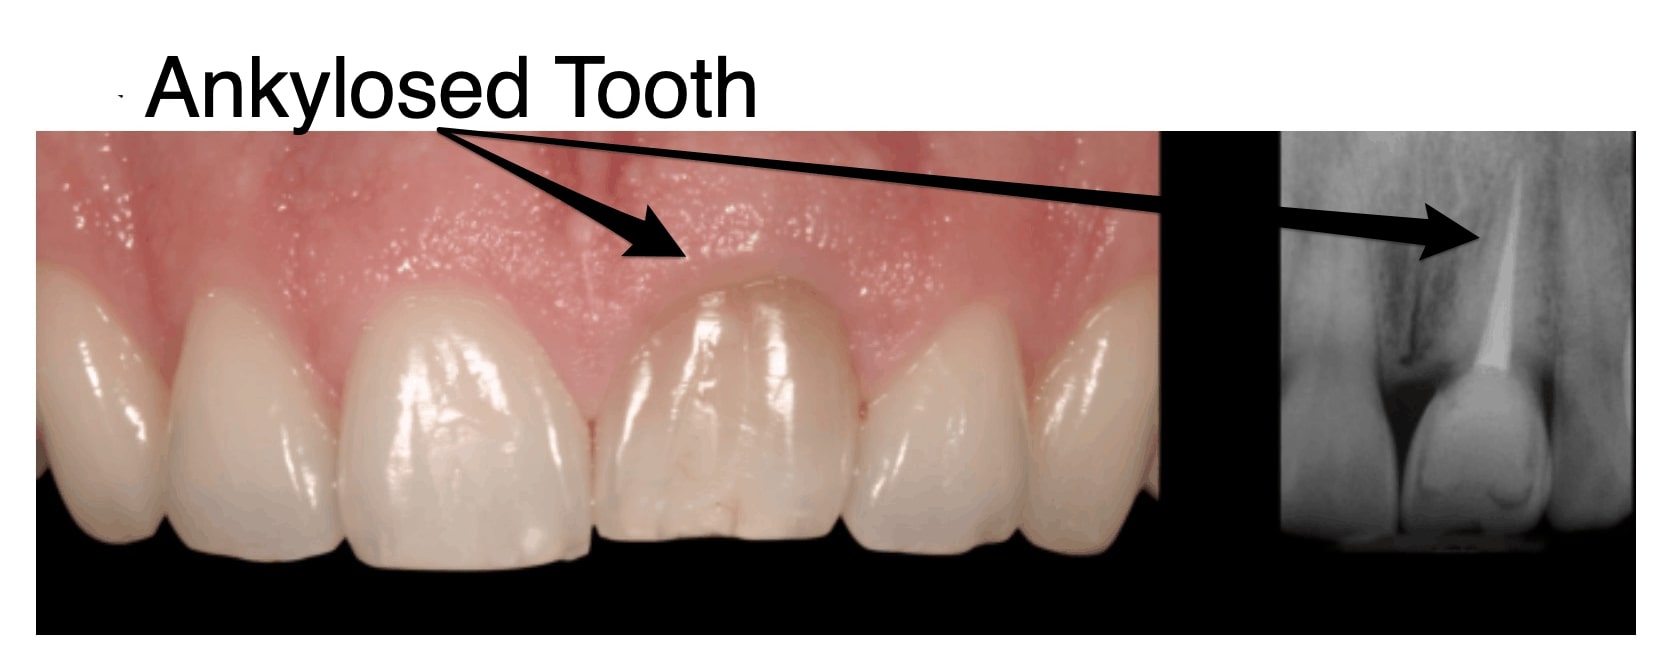

آنکیلوز دندان و به اصطلاح دندان فک جوش که در دنیای دندانپزشکی نادر است، شامل آمیختگی ریشه دندان با استخوان اطراف است که از حرکت طبیعی و رویش دندان در حفره دهان جلوگیری می کند. این همجوشی به دلیل وقفه در روند طبیعی رویش دندان و اتصال به استخوان رخ می دهد. از هدایت صحیح دندان به موقعیت مورد نظر خود در قوس دندانی جلوگیری می کند و منجر به اتصال غیر طبیعی بین ریشه دندان و استخوان اطراف می شود.

عکس گرافی دندان فک جوش

نتیجه این اختلالات، آمیختگی ریشه دندان با استخوان اطراف است و از حرکت بیشتر دندان در مسیر رویش خود جلوگیری می کند. این عارضه می تواند نه تنها بر روی تراز دندان آسیب دیده بلکه بر روی دندان های مجاور و سلامت کلی دهان نیز تاثیر بگذارد. دندان های انکیلوز شده بیشتر با دندان عقل (مولر سوم) مرتبط هستند و می توانند منجر به عوارض مختلفی از جمله نهفتگی، ناهماهنگی و چالش در حین کشیدن دندان فک جوش و یا دندان عقل فک جوش شوند. تشخیص دندان فک جوش اغلب شامل ارزیابی بالینی و رادیوگرافی کامل برای ارزیابی درجه آنکیلوز و برنامه ریزی استراتژی های درمانی مناسب است.

تشخیص آنکیلوز دندان از طریق ترکیبی از معاینه بالینی و تکنیک های تصویربرداری پیشرفته تشخیص داده می شود. در طول ارزیابی بالینی، متخصصین دندانپزشکی قوس دندانی بیمار را بازرسی می کنند و موقعیت، تحرک و تراز دندان را ارزیابی می کنند. با این حال، مشخصه آنکیلوزدندان عدم تحرک طبیعی آن است. برای تایید تشخیص و ارزیابی میزان آنکیلوز، از ابزارهای تصویربرداری پیشرفته مانند توموگرافی کامپیوتری با پرتو مخروطی (CBCT) استفاده میشود. عکس CBCT تصاویر سه بعدی از دندان ها و ساختارهای اطراف را ارائه می دهد و رابطه پیچیده بین دندان انکیلوز و استخوان مجاور دندان را آشکار می کند. این تصاویر دقیق به تعیین شدت آنکیلوز کمک می کند، که برای برنامه ریزی استراتژی های درمانی مناسب حیاتی است.